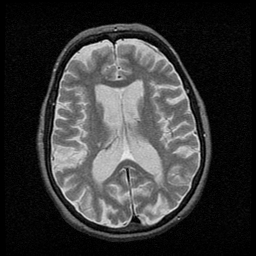

Huntington's Chorea, MR -- Slice #11

[Home][Help][Clinical] Slice 11